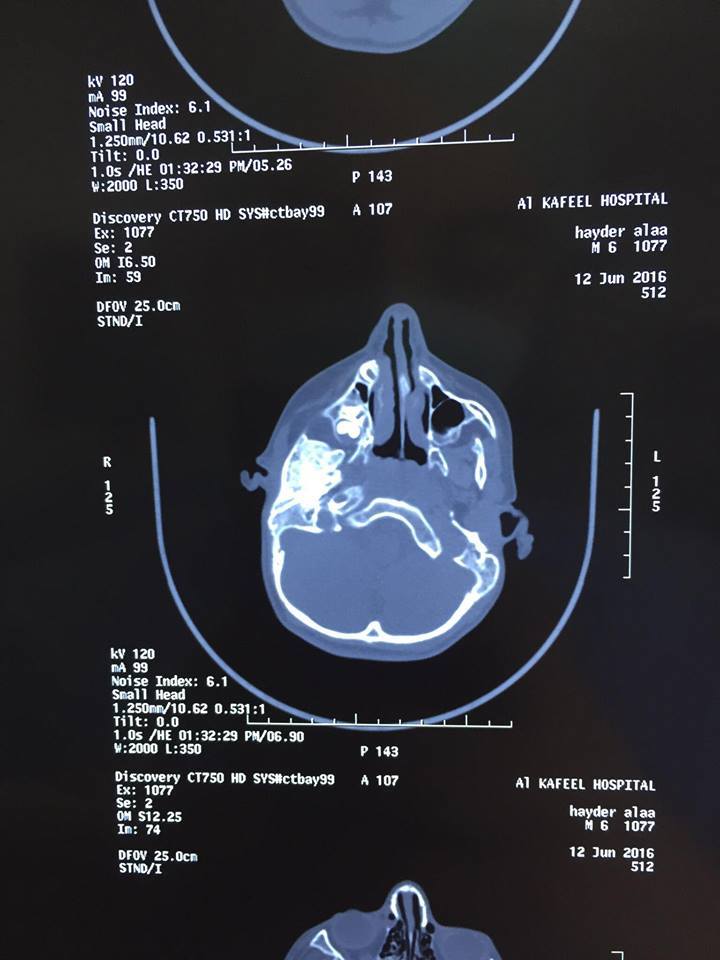

زُرعت احد إضلاع طفل في السادسة من العمر لتكوين مفصل فك جديد له، لإصابته بتشوه ولادي بالوجه والفكين في مستشفى الكفيل التخصصي بكربلاء. وقال أخصائي جراحة الوجه والفكين الدكتور مهند صلاح لوكالة نون الخبرية أنه أستطاع بمساعدة أخصائي جراحة الصدر الدكتور صفاء العلي من إجراء عملية لطفل في السنة السادسة من عمره يعاني من تشوه ولادي بالوجه، وفاقد لمفصل الفك بالكامل، وهو غير قادر على الأكل، ولا يستطيع مضغ الطعام، وفاقد للغده اللعابية، حيث تمثلت العملية بتكوين مفصل فك جديد من خلال زراعة احد إضلاعه ووضعه بدل مفصل الفك. وأضاف صلاح إن العملية استمرت أكثر من خمس ساعات وتعتبر نادرة من نوعها لأن هكذا تشوه يصيب شخص واحد لأكثر من مائة إلف شخص، وان هذه العملية ستُساعد في تحسين وضع الطفل النفسي و مساعدته بالقدرة على الأكل بشكل أفضل. فيما أشارت الإعلامية في قسم العلاقات والإعلام بمستشفى الكفيل التخصصي هبة الصباغ لوكالتنا أن أخصائي الأنف والاذن والحنجرة الدكتور عادل المسعودي كان قد أجرى عملية للطفل المذكور أعلاه سبقت هذه العملية لتوسعت القصبات الهوائية. محسن الحلو وكالة نون/خاص